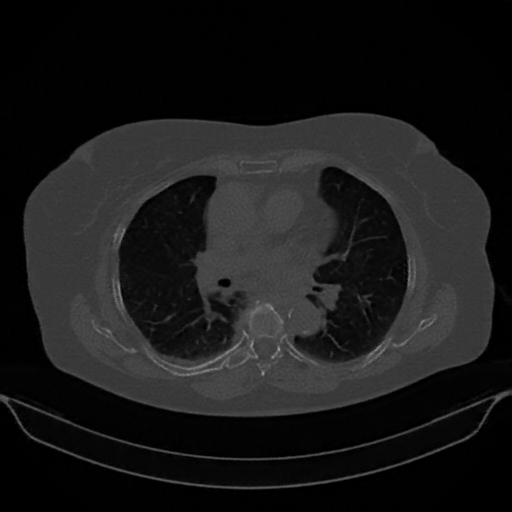

Image Grid

4Γ—3 grid: Rows show different image types (Original NATIVE, Reconstructed NATIVE, Original VENOUS, Generated VENOUS), Columns show windowing techniques (No Window, Lung Window, Mediastinum Window)

Original NATIVE CT scan (input)

Lung window (WL -600, WW 1500 β†’ Low βˆ’1350, High +150)

Generated VENOUS CT scan (A→B translation)